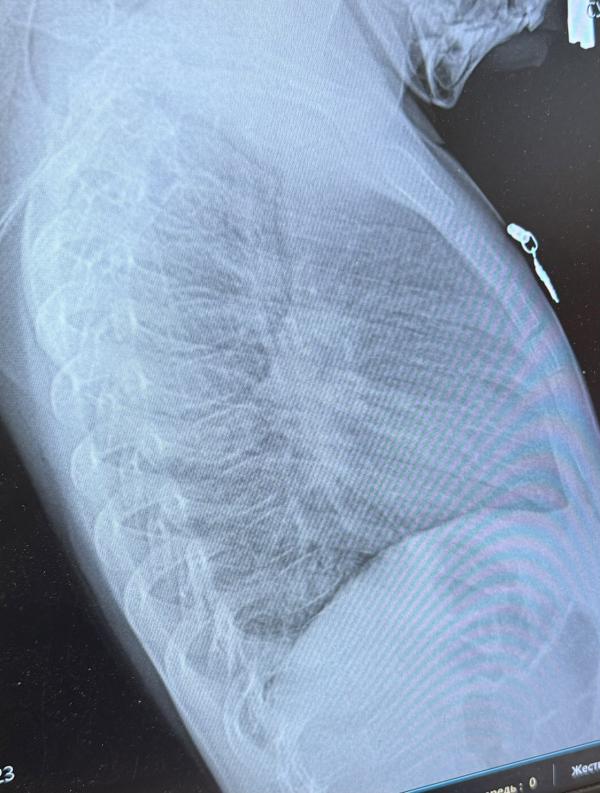

Симптомы пневмонии у детей: как распознать и что делать

Девочки кто понимает,есть пневмония ?